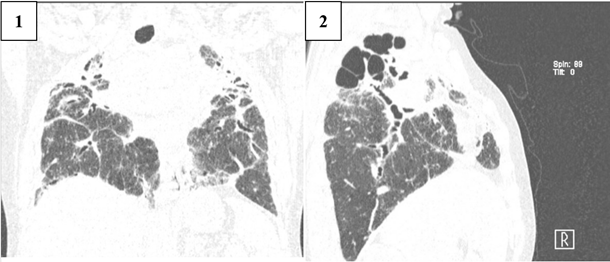

/Nukusheva.files/image009.png)

Figure 9. CT scan of Patient K., a 47-year-old male, showing the appearance of Stage IV clinical sarcoidosis